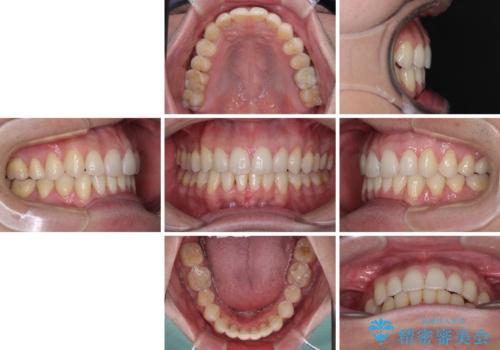

ディープバイトと叢生 インビザラインによる矯正治療

上下ともに叢生が認められたため、親知らずすべてを抜歯し、歯列全体を後方へ移動させることで歯列を整えることとしました。

上顎奥歯の銀歯も気になっていたので、矯正治療の途中でセラミッククラウンへ変更し、その後歯列を仕上げていくこととしました。

ディープバイトもデコボコも改善され、気になっていた銀歯もセラミックとなり、患者様には大変満足していただきました。